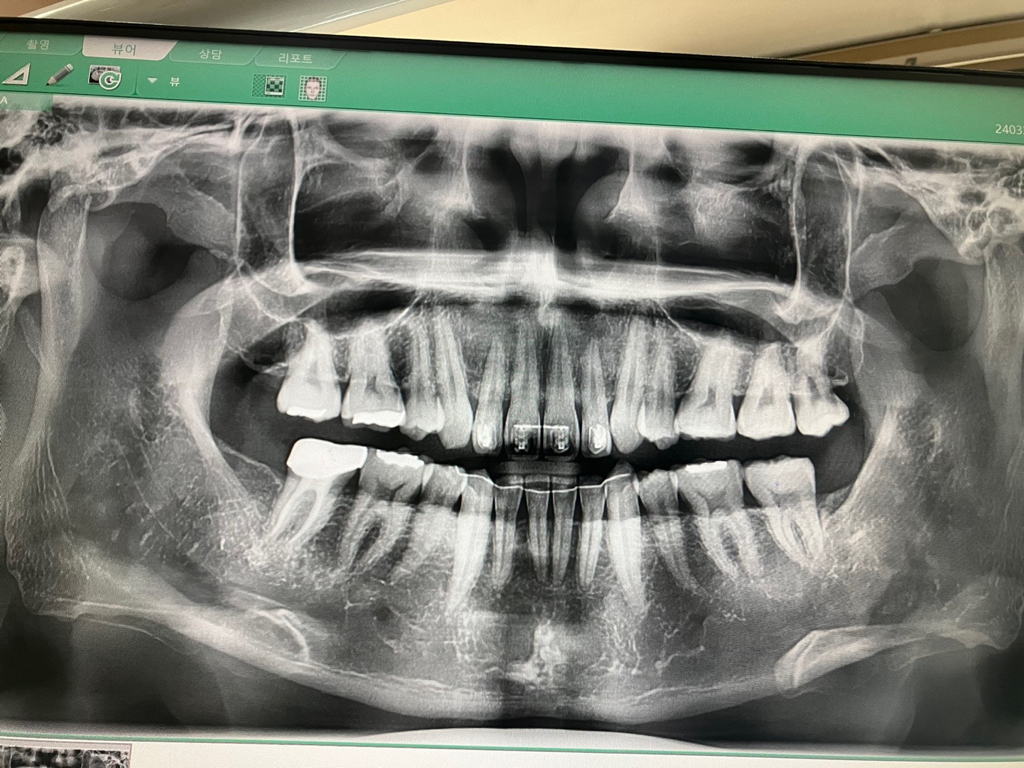

치주인대가 회복하는 과정에서 잇몸이 붓기도 하나요?

5일전에 교합외상때문에 치아를 살짝 갈았습니다.

오룬쪽 아래 소구치 입니다

• 1번 째 사진